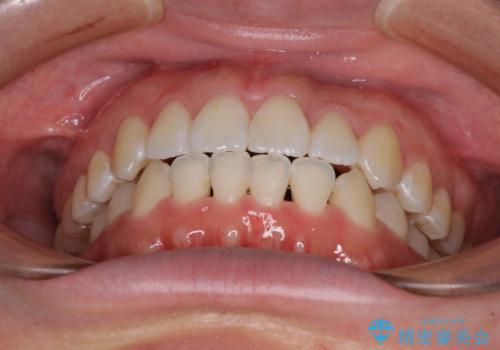

前歯のデコボコを治したい ワイヤー矯正

咬み合わせが安定し、前歯の汚れも付きにくくなりました。

奥の銀歯も気になっていたため、矯正治療後にセラミッククラウンにて補綴することとしました。